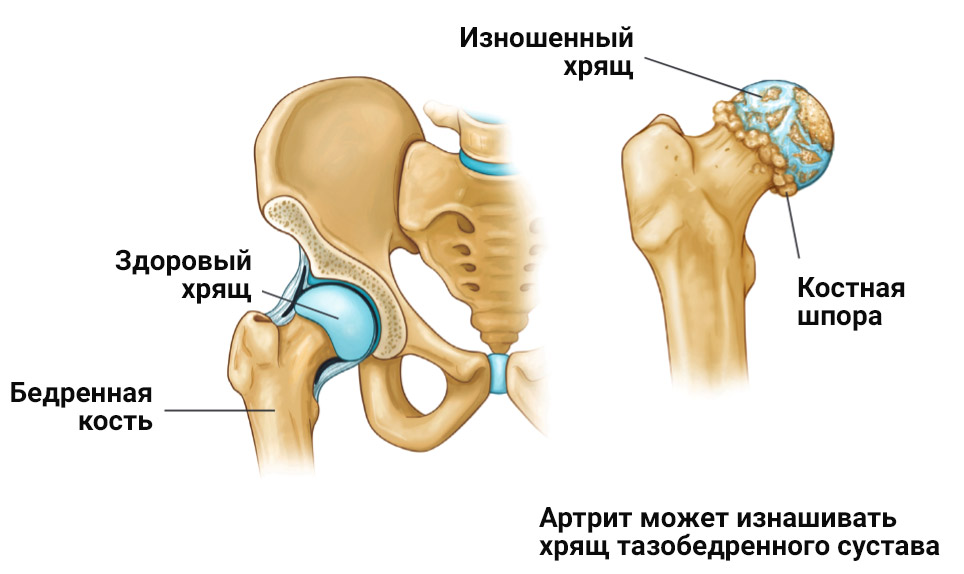

Фотографии и схемы: Коксит правого тазобедренного сустава